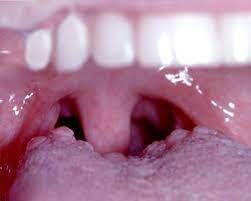

Bumps on the Back of the Tongue

What are Tongue Bumps? What Do They Look Like?

A healthy tongue is normally covered in small bumps called papillae. Some of them contain taste buds. They give the tongue its distinctive texture.1

Your papillae are often unnoticeable because they have a consistent color and texture. However, some conditions can cause them to become inflamed.

Inflamed papillae can appear raised or enlarged. They may cause your tongue to feel painful, sore, or unusually sensitive.